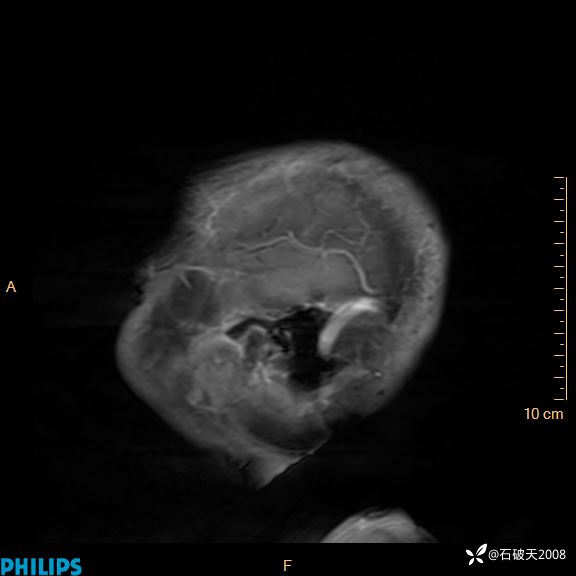

2020.11.14MR

增强矢状位